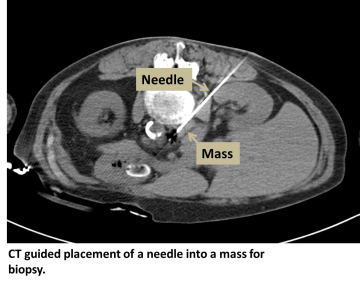

How it’s done:

An interventional radiologist uses CT or ultrasound to pass an introducer needle into the tissue of interest. Once position is confirmed, a biopsy needle is passed through the introducer needle and used to take samples until adequate tissue is obtained.